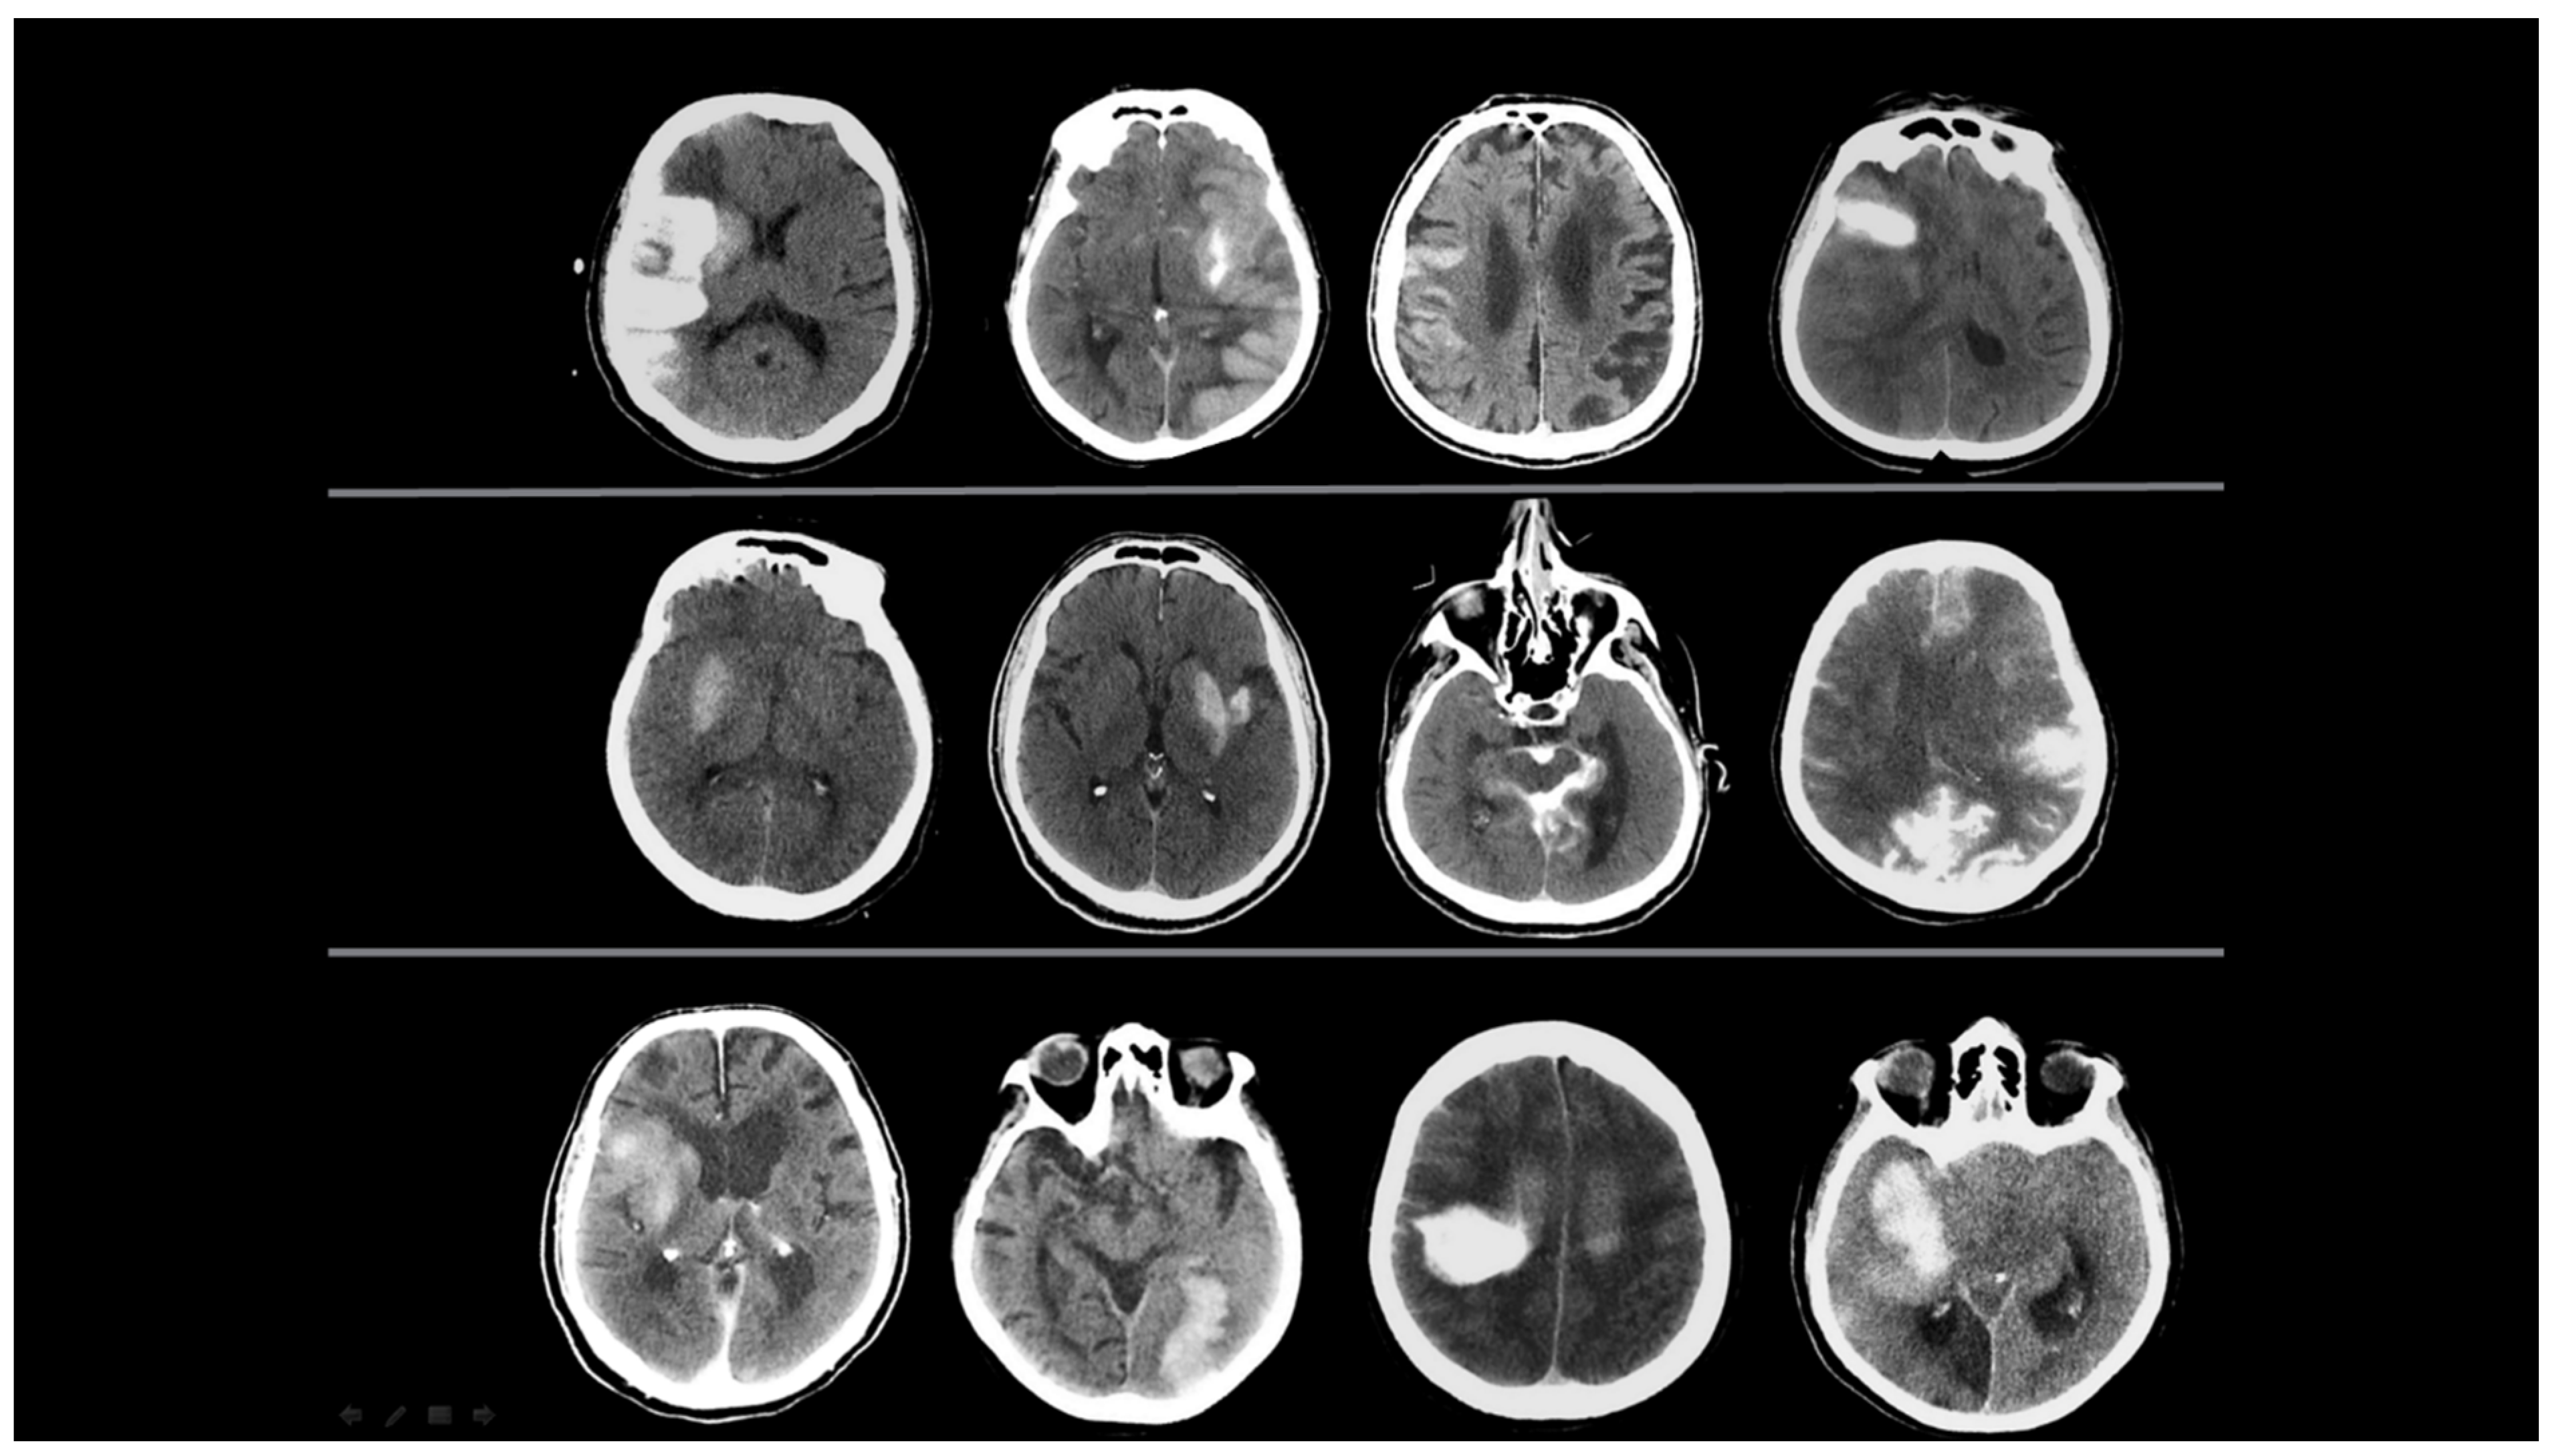

The representative images of the labeled patients evaluated by radiologists are shown in Figure 2 and Figure 3.

Figure 2.

Initial and follow-up NCCT scans of four different patients with ‘contrast accumulation’. CASE 1: A 55-year-old male patient was evaluated with initial NCCT within the first 24 h after complete recanalization (TICI 3) following occlusion of the left MCA M2. Hyperdense areas seen at the level of the left caudate nucleus and lentiform nucleus decreased and disappeared on subsequent follow-up NCCT scans taken 24 h later. CASE 2: A 38-year-old female patient, after complete recanalization (TICI 3) following right ICA occlusion, during the initial NCCT examination within the first 24 h, showed more pronounced hyperdensity areas at the level of the right lentiform nucleus and in the MCA perfusion area cortex, which decreased and disappeared in the follow-up NCCT scans 24 h later. CASE 3: An 85-year-old female patient underwent EVT, which was completed with complete recanalization (TICI 3) after left ICA occlusion. The initial NCCT scan performed within the first 24 h showed hyperdense areas in the cortical territory of the left MCA, which disappeared in the follow-up NCCT scan taken 24 h later. CASE 4: A 52-year-old male patient presented with complete recanalization (TICI 3) after EVT due to occlusion of the superior trunk of the left MCA M2 segment. In the NCCT scan (initial NCCT) performed within the first 24 h after the procedure, an area of hyperdensity in the left insular cortex and its lateral region decreased and resolved in the subsequent follow-up NCCT scans taken 24 h later.

Figure 3.

Initial and follow-up NCCT scans of four different patients with ‘hemorrhagic transformation’. CASE 1: An 86-year-old male patient, after EVT was completed with complete recanalization (TICI 3) following right ICA occlusion, underwent an initial NCCT examination within the first 24 h, which showed hyperdense areas in the right basal ganglia, insular cortex, and MCA watershed area in the cortex. These hyperdense areas were still present on the 38-h follow-up NCCT scan. CASE 2: A 78-year-old female patient with right MCA M2 occlusion; the initial NCCT examination taken within the first 24 h after EVT concluded showed areas of hyperdensity in the right temporal lobe, in the subarachnoid space, and in the tentorium, which were still present 32 h after the NCCT scan.